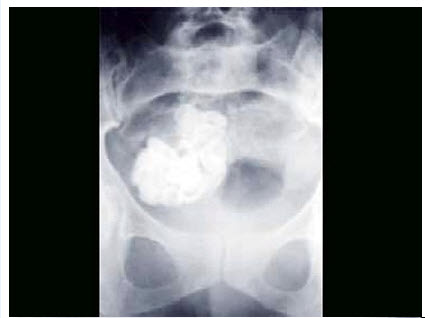

18、单项选择题

男,根据其正常骨盆影像图像,判断其最可能的年龄()

A.2岁左右

B.8岁左右

C.6岁左右

D.12岁左右

E.10岁左右